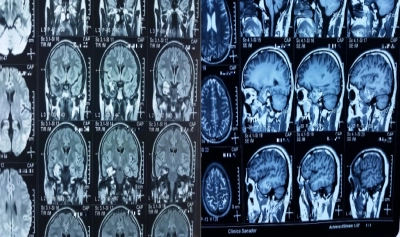

La recomandare neurologului, Ștefan a mers la dr. Ovidiu Grămescu, Medic primar Neurochirurgie și Șeful Secției de Neurochirurgie din cadrul Spitalului Clinic Sanador care, după confirmarea diagnosticului, a programat intervenția câteva zile mai târziu. Operația a avut loc în iunie 2017, a durat circa 4 ore și a fost efectuată sub lentila minuțioasă a microscopului operator Zeiss Kinevo 900 – unic în România, echipament chirurgical de calitate superioară, sistem de neuronavigatie și aspirație tumorală.

„Totul este important când vine vorba de intervențiile neurochirurgicale. Contează experiența echipei operatorii – zecile de ani de practică, omogenitatea echipei operatorii, dar și tehnologia de ultimă generație din sala de operație. La Sanador folosim, printre altele, microscopul operator Zeiss Kinevo 900 – unic în România, sistem de neuronavigație cerebrală Medtronic, sistem de aspirație cerebrală (CUSA), aparat ce monitorizeaza potențialele nervului facial intraoperator - EMG nerv facial -, util în tumorile de cerebel și trunchi cerebral”, ne arată Dr. Ovidiu Grămescu.